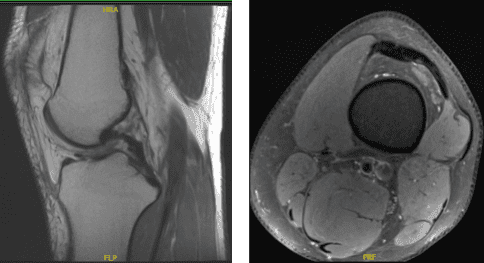

MRI Impression as follows: Oblique tear in the posterior horn of the medial meniscus extending to the inferior surface, peripheral third. Edema in the superolateral aspect of Hoffa’s fat pad suggestive of Hoffa’s fat pad impingement and elevated TT TG distance of 16 mm which can be seen in setting of patellofemoral maltracking and small popliteal cyst.